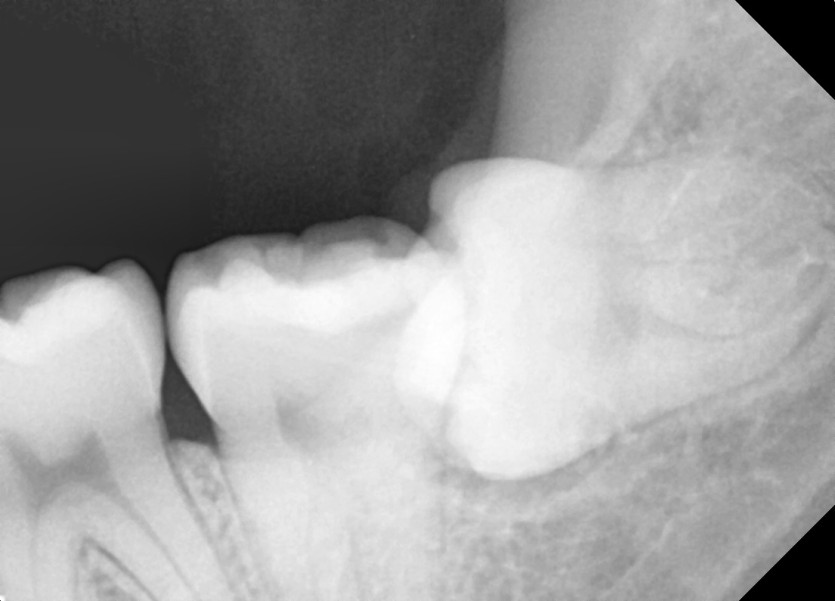

#28,38 사랑니 발치

구강 외과 전문의가 당일 발치했습니다.